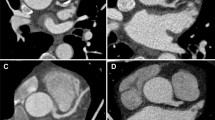

The 18 included studies encompassed 3,568 patients and 13,362 vascular images. These studies were published between 2019 and 2023, and these studies were conducted in China, the United States, Australia, Japan, Mexico, Portugal, and the Netherlands. Five studies were multicenter studies [25, 32, 33, 35, 37], while the remaining were single-center studies. Regarding image sources, 3 studies relied solely on CAG images [27, 28, 31], 11 utilized only CCTA images [4, 24,25,26, 28,29,30, 33, 37,38,39], and 4 used both modalities [27, 32, 35, 36]. Twelve studies used binary classification tasks [24,25,26, 28, 29, 31, 32, 34,35,36], while six focused on multiclass tasks [4, 27, 30, 33, 37, 38]. The threshold for defining coronary artery stenosis varied across studies, with > 25%, > 50%, and > 70% being the most commonly used. Five studies used 25% as the threshold for defining coronary artery stenosis [26, 28, 30, 33, 37], seven used 50% [24, 25, 28, 32, 36,37,38], four used 70% [30, 33, 37, 38], and two did not explicitly define the threshold [4, 35]. Detailed information is provided in Table 1.

Based on vascular images, the meta-analysis showed that the accuracy of CCTA-based models was 0.80 (95% CI: 0.76–0.84) for detecting < 50% stenosis, 0.76 (95% CI: 0.53–0.99) for > 50% stenosis, 0.81 (95% CI: 0.76–0.84) for < 25% stenosis, and 0.81 (95% CI: 0.75–0.88) for > 25% stenosis (Fig. 4). Based on patients, the meta-analysis revealed that the accuracy of these models was 0.87 (95% CI: 0.67–1.07) for detecting < 50% stenosis, 0.70 (95% CI: 0.62–0.79) for > 50% stenosis, 0.85 (95% CI: 0.81–0.90) for < 25% stenosis, and 0.72 (95% CI: 0.62–0.82) for > 25% stenosis (Fig. 5).